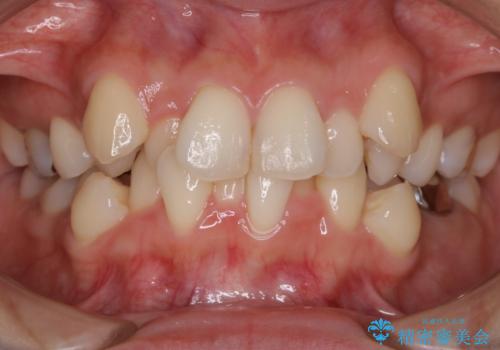

デコボコと変色した前歯 抜歯矯正と審美歯科治療